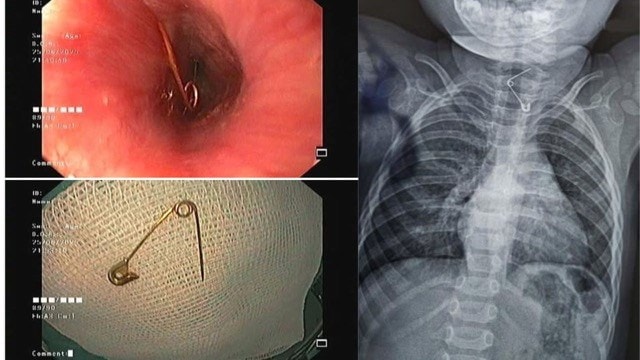

Vừa qua, Khoa Tiêu hóa - Bệnh viện Nhi Đồng 2, Tp.HCM tiếp nhận ca cấp cứu nguy kịch: bệnh nhi P.P.K. 1 tuổi ở Đồng Nai nhập viện trong tình trạng đau đớn và nguy cơ thủng thực quản do nuốt một cây kim băng dài khoảng 3 cm.

Tại khoa Cấp cứu, các bác sĩ tiến hành thăm khám và nội soi khẩn cấp. Kết quả cho thấy cây kim băng đã bung ra hình chữ L, đầu nhọn ghim vào thành thực quản gây nguy cơ thủng, xuất huyết và nhiễm trùng nặng. Đây là tình huống đòi hỏi xử lý nhanh chóng, chính xác và cẩn trọng để bảo vệ tính mạng và sức khỏe của bệnh nhi.

Tiếp đó, ê-kíp liên chuyên khoa gồm Tiêu hóa - Tai Mũi Họng - Ngoại khoa, Bệnh viện Nhi đồng 2 TpHCM được huy động để hội chẩn và triển khai phương án can thiệp. Sau quá trình xử lý nội soi tỉ mỉ, các bác sĩ đã lấy được dị vật mà không cần phẫu thuật mở. Nhờ sự phối hợp nhịp nhàng giữa các chuyên khoa, ca cấp cứu đã diễn ra an toàn, bé được cứu khỏi một tình huống nguy hiểm.